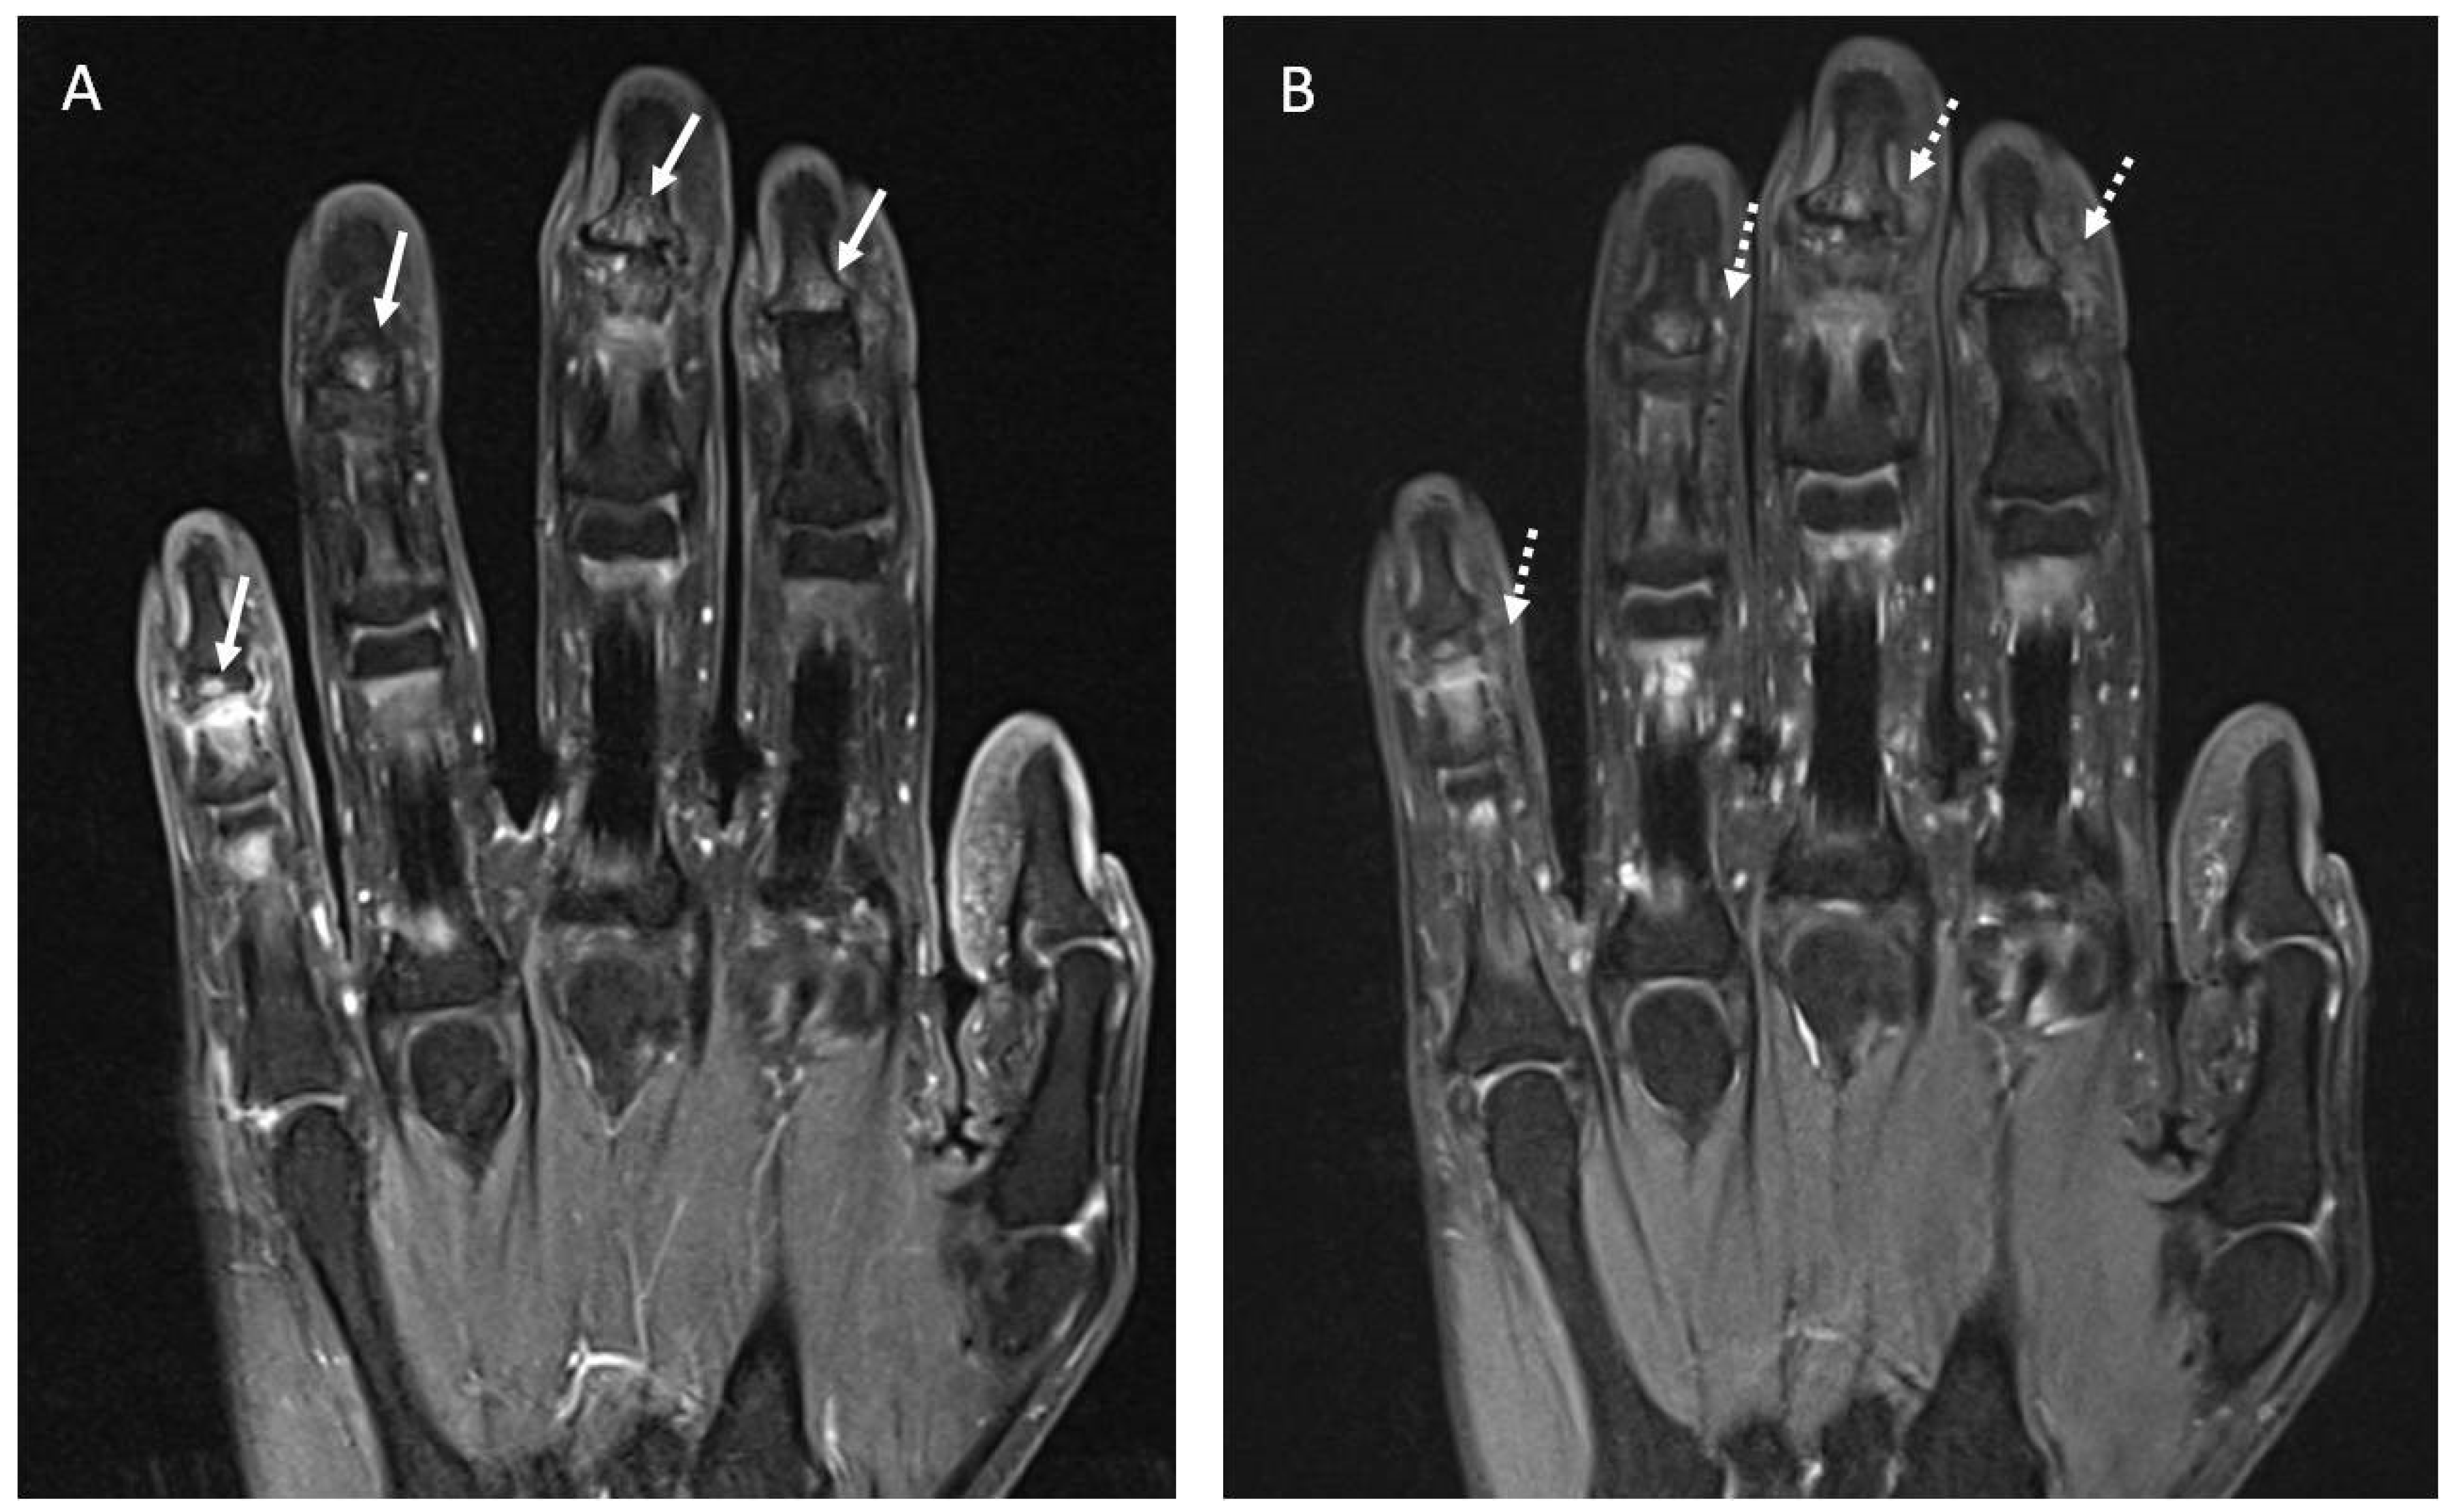

Figure 5. (A). Coronal fat suppressed T1-weighted image of the hand following IV contrast administration shows small areas of contrast enhancement of the subcortical articular margin (arrows) of the distal interphalangeal joints in the second, third, fourth and fifth fingers consistent with inflammatory activity. (B). Coronal fat suppressed DP-weighted image of the hand shows areas of bone edema of the subcortical articular margin (dashed arrows) of the distal interphalangeal joints in the second, third, fourth and fifth fingers.

Four patients underwent MRI assessment. Two patients received treatment with Anti-TIM3, one with Pembrolizumab, and one with Durvalumab. In these patients, ICI-induced arthritis appeared after a mean time of 15.5 months. Abnormal findings were reported in three out of four patients, all in accordance with clinical symptoms. One patient presented with a PsA-like pattern and had signs of distal bone edema in the fingers (Figure 5). No erosions or myofascitis were reported. The general characteristics of previous cases reported with rheumatic irAEs and MRI assessment are shown in Supplementary Table S1.